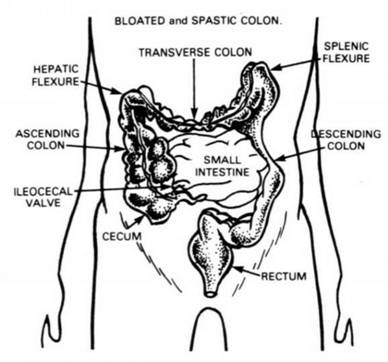

19. The Splenic Flexure of the Colon, or the bend in the Colon leading from the Transverse Colon (No. 22 and No. 23) to the Descending Colon (No. 31).

22. The Transverse Colon, frequently becomes a gas storage balloon when 23 . tense nerves or impactions of waste matter in the Flexures (Nos. 21-29) prevent the gas from expanding and being expelled. Asa result of improper nourishment this section of the Colon easily loses its tone and then sags, causing what is more picturesquely described as a prolapsus.

GOOD MORNING! How is Your Colon this Morning? How the Colon functions. A Blocked Colon! Exercises to help the Colon

Study sketch.

ABOVE What a person's Colon should be.

BELOW: What happens when the COLON FAILS TO RECEIVE NECESSARY COLON IRRIGATIONS.